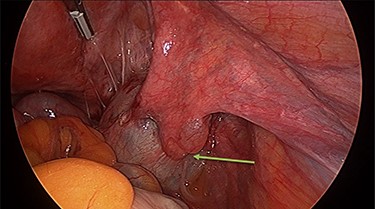

Operation findings consisted of left hydrosalpinx and para-tubal cyst adhered to pouch of douglas, with the left tube torted 3 times (Figs 4 and 5). There was a 5-cm para-tubal cyst on the right tube adhered to right side of pelvis/rectum/pouch of douglas (Fig. 6). The ovaries appeared normal.

Diagnostic laparoscopy is the only method of confirming tubal torsion [6]. Surgical technique for correcting isolated tubal torsion may include conservative (detorsion) or definitive management (salpingectomy). Choice of management will be influenced by patient factors including age, completion of fertility and symptoms, as well as surgical factors including ease of detorsion, appearance of revascularization and associated pelvic pathology. Because isolated tubal torsion is difficult to distinguish clinically from differential diagnoses, delay in surgical exploration often leads to necrotic appearances of the tube, requiring salpingectomy [5].